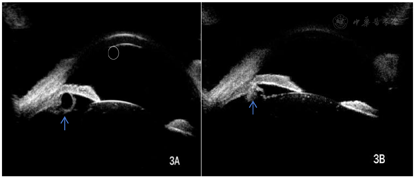

免疫球蛋白A 5.73 g/L,免疫球蛋白M 0.42 g/L,补体C3 0.664 g/L,抗nRNP抗体阳性(+++),抗核小体抗体阳性(++),抗核糖体P蛋白抗体阳性(+++),抗核糖体-核型1核均质型(AC-1),抗组蛋白抗体阳性(++),核型1滴度阳性1:1280,白细胞计数1.74×109/L,红细胞沉降率:30 mm/h,尿蛋白:+。眼科检查:视力右:1.0,左:0.8,眼压右:15 mmHg(1 mmHg=0.133 kPa),左:14 mmHg,双眼睑未见明显异常,睑球结膜无充血,角膜透明,前房深度适中,房水清,虹膜纹理清,瞳孔圆,直径约3 mm,对光反射灵敏,晶状体周边可见散在白色小片状混浊,右眼下方玻璃体腔内可观察到一半透明圆形悬浮物,表面上可见少量色素附着,且囊壁光滑,并随眼球运动,散瞳后右眼眼底可见视盘界清,色红润,血管走形正常,A:V=2:3,视网膜平伏,黄斑区中心凹反光可见(图1A),左眼眼底可见视盘界清,色红润,颞上方血管弓静脉走形稍迂曲,视网膜平伏,黄斑区中心凹反光可见(图1B)。眼部B超示:右眼可见一环形中高回声(图2)。超声活体显微镜(UBM)示:双眼睫状体6点位各见一囊肿,囊肿呈圆形,囊内为无回声区,外周回声与睫状体回声强度基本相同的回声(图3A、图3B)。眼前节照相示:右眼玻璃体腔内有半透明圆团状囊样悬浮物,其表面有棕黄色色素沉着(图4)。初步诊断为:右眼玻璃体囊肿、双眼睫状体囊肿、双眼先天性白内障、系统性红斑狼疮。

诊断依据:患者,女性,25岁,因反复发热、四肢多关节疼痛伴皮疹40 d,患者自觉右眼眼前有明显的漂浮物,眼科检查:视力右:1.0,左:0.8,眼压右:15 mmHg,左:14 mmHg,晶状体周边可见散在白色小片状混浊,右眼下方玻璃体腔内可观察到一半透明圆形悬浮物,表面上可见少量色素附着,且囊壁光滑,并随眼球运动,眼部B超示:右眼可见一环形中高回声。超声活体显微镜(UBM)示:双眼睫状体6点位各见一囊肿,囊肿呈圆形,囊内为无回声区,外周回声与睫状体回声强度基本相同的回声。眼前节照相示:右眼玻璃体腔内有半透明圆团状囊样悬浮物,其表面有棕黄色色素沉着,结合患者眼部B超、超声活体显微镜、眼前节照相表现可诊断为玻璃体囊肿及睫状体囊肿。

相关文献表明,玻璃体囊肿患者可伴有无虹膜或睫状体囊肿[10],本例患者的诊断即为玻璃体囊肿并伴有睫状体囊肿。原发性的睫状体囊肿多为单眼发病,生长较为缓慢,多见于睫状沟内,通常情况下未见明显的临床症状[11]。既往研究表明,无论是单一的睫状体囊肿还是多发的双侧睫状体囊肿,多为良性改变,但伴随着其不断生长,也容易顶起巩膜根部,从而导致周边前房的深度变浅,使房角粘连范围扩大,从而进一步导致房角的关闭,眼压也随之增高,这种情况和闭角型青光眼有相似之处[12],应及时进行评估,避免误诊或漏诊而延误病情,同时加强患者定期随访尤为重要[13]。